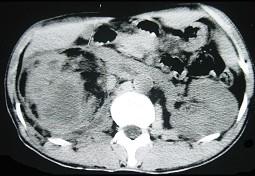

问题 女,43岁,右腰部疼痛不适2年余,加重3天,CT及MR检查如图,应诊断为 ( )

选项 A、右肾脂肪肉瘤 B、右肾海绵状血管瘤 C、右肾错构瘤合并出血 D、右肾脂肪瘤 E、右肾癌

答案 C